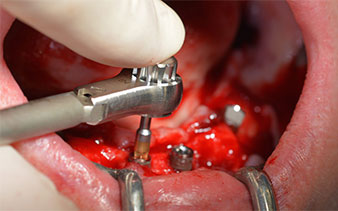

A continuación, se identificó el agujero mentoniano (foramen mentale) como la estructura anatómica límite y se alisó el cortical de la cresta ósea con la pieza de mano recta y una fresa redonda grande (fig. 4).

El protocolo quirúrgico de los implantes utilizados (SKY, bredent medical) prescribe una velocidad de 1 200/rpm para las perforaciones piloto (figs. 7-9).

Este valor se corresponde con la posición siguiente del ajuste predefinido en Implantmed. Aquí se aprecia la inclinación de aproximadamente 45 grados del contra-ángulo de W&H hacia medio caudal en la región de la pieza 45 para preservar el nervus mentalis. El foramen mentale sirve como orientación anatómica para todas las perforaciones en esta zona. Las perforaciones siguientes se realizaron con una velocidad reducida de 300/rpm (figs. 10 y 11).